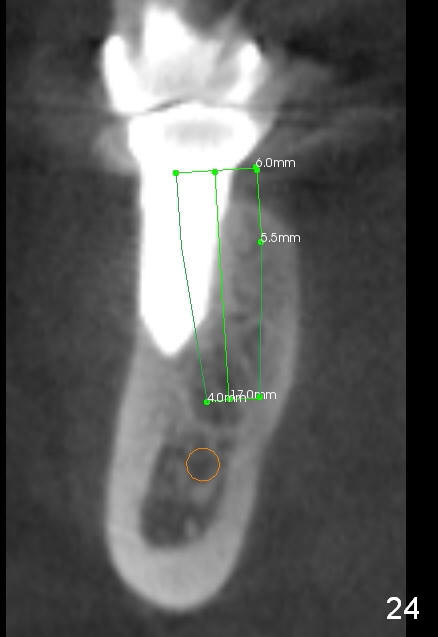

CBCT taken 15 months post cementation shows that the implant is buccally placed (Fig.21 B), associated with possible postop buccal plate resorption (as compared to Fig.23 (coronal section of the site of #19). The buccal plate is not only thinner than the lingual one, but also concave (Fig.22 <). The tooth center (i.e., septum; Fig.23 T) is more buccally located than the center of the basal bone (B). Considering the denser bone lingually, the initial osteotomy should be more lingually (^). If the implant develops infection, it will be replaced by a more lingually placed implant (Fig.24 green).